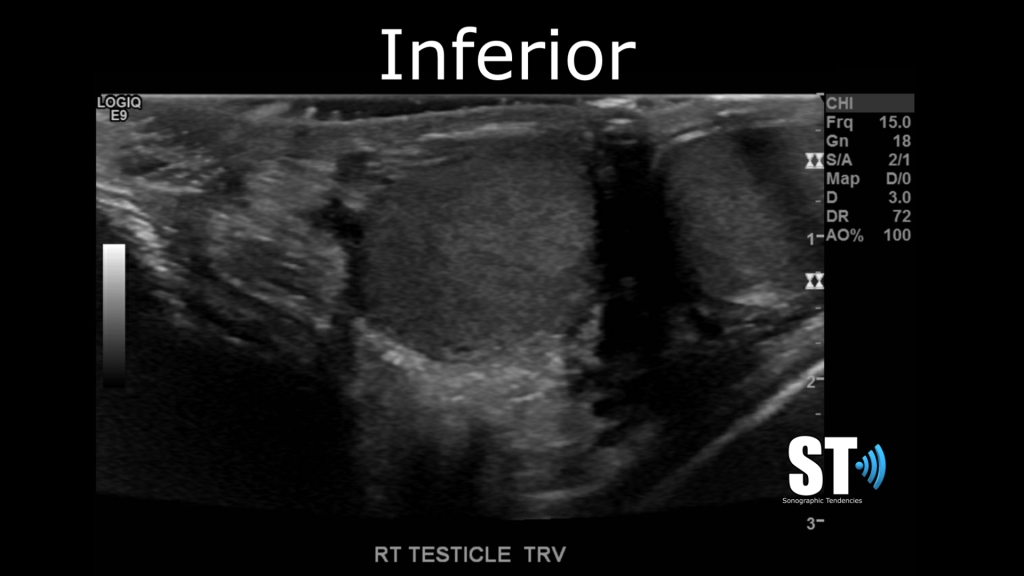

Transverse

In transvers beginning at the superior pole take images of starting at the epididymal head and capture images of the superior, mid section and inferior poles of the testis.